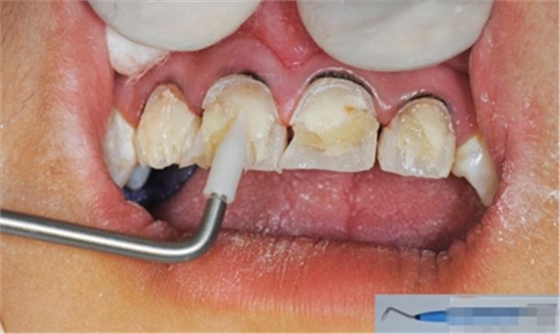

【分層堆塑】

A4本質(zhì)堆塑

A3本質(zhì)堆塑

發(fā)育葉制作

白堊斑

切端琥珀色制作

A3頸部堆塑

涂布防氧化劑

充填初步完成